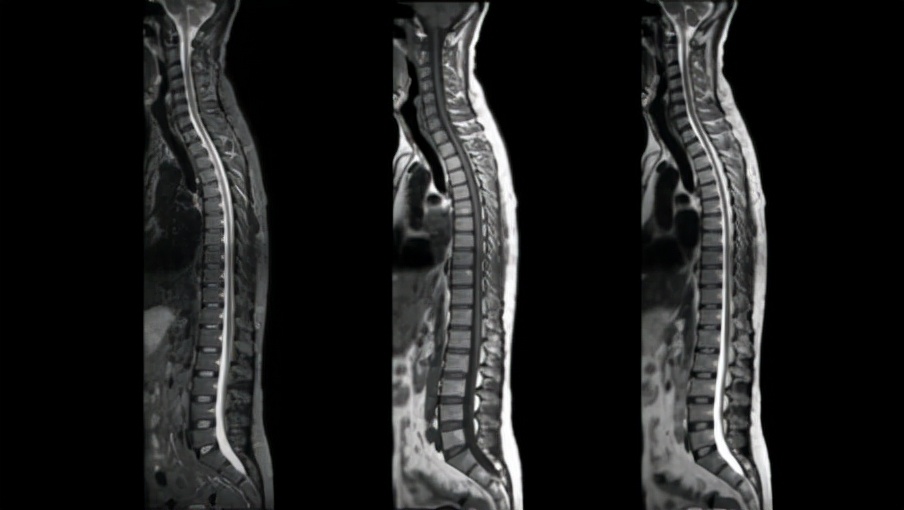

MR 5300大(55 厘米)视场提供了更大的解剖覆盖范围,同时其强大的AI驱动扫描方法和易于定位的超轻量dStream Breeze线圈相结合产生优质的图像质量,尤其是在对具有挑战性的解剖结构,如脊椎、腹部进行成像时比。通过简化、自动化捕获高质量图像所涉及的复杂临床和操作任务,MR 5300提高了放射科输出的一致性和生产力,有助于提高患者满意度和转诊率,其无氦操作使其适用于门诊和专门的放射科。